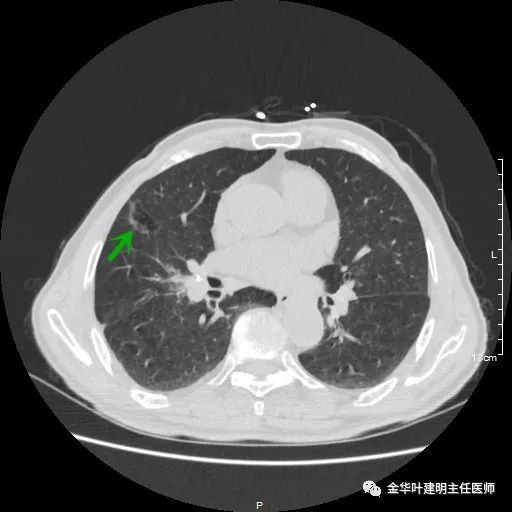

以上示左上叶病灶2。病灶虽然似慢性炎,但有收缩力,有毛刺征,在右侧诸多病灶考虑多原发肺癌的前提下,此灶是恶性的可能性非常大,不能单纯认为其是慢性炎性病灶。就此单灶来看,可以局部切除病检,若示浸润性腺癌,则有肺叶切除的指征。